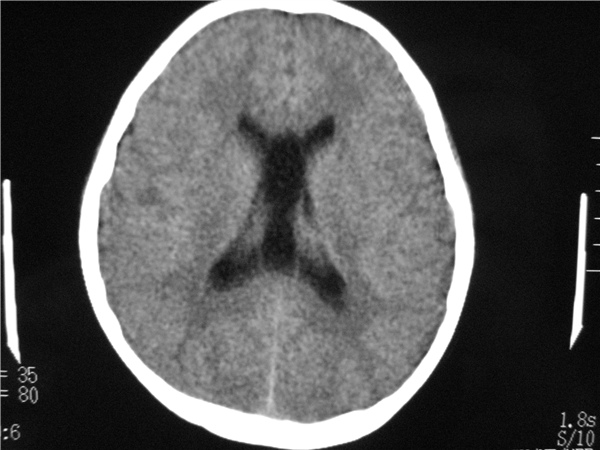

以下是引用随光逐影在2009-8-1 14:17:00的发言:[br]透明隔囊肿与vergae腔并存。

以下是引用zjzjr在2009-8-1 14:51:00的发言:[br]五、六脑室形成。